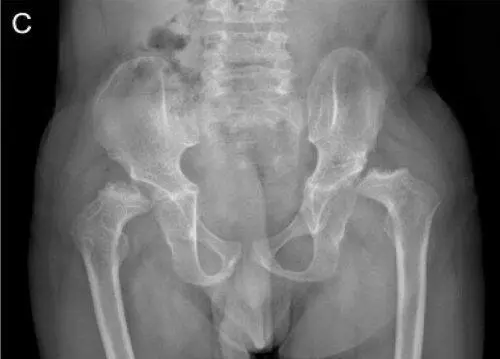

Синдром Wolcott-Rallison.Синдром назван в честь врачей Wolcott С. D., Rallison М. V. впервые в 1972 году, описавших трех больных в одной семье, имевших сочетание неонатального диабета и спондилоэпифизарных нарушений скелета [207]. Это аутосомно-рецессивное заболевание, характеризующееся ранним началом сахарного диабета, обычно в неонатальный период, и спондилоэпифизарными нарушениями роста. У больных часто отмечается гепатомегалия, задержка умственного развития, почечная недостаточность, ранняя смерть. В 2000 году Delepine М. et al. [66] описали двух подобных детей в разных семьях, имеющих мутацию 2р12. В данном локусе находится ген, являющийся регулятором синтеза инсулина и белков в β-клетках поджелудочной железы. В мире к 2010 году были описаны около 60 пациентов с синдромом Wolcott-Rallison (Julier С., Nicolino М., 2010) [116]. Хотя, конечно, больных небольшое количество, но, тем не менее, некоторые закономерности течения данного синдрома понятны. Сахарный диабет развивается в первые шесть месяцев жизни, спондилоэпифизарные нарушения роста начинают проявляться в первые два года жизни. Они выражены как клинически, так и рентгенологически (рис. 15–16).

Рис 15 Рентгенограммы пациента с синдромом WolcottRallison возраст 13 лет - фото 40 Рис 15 Рентгенограммы пациента с синдромом WolcottRallison возраст 13 лет - фото 41 Рис 15 Рентгенограммы пациента с синдромом WolcottRallison возраст 13 лет - фото 42

Рис. 15. Рентгенограммы пациента с синдромом Wolcott-Rallison (возраст 13 лет)

(Julier С., Nicolino М., 2010) [116].

А — руки: кости запястья небольшие с дисплазией дистального отдела лучевого и локтевого эпифизов; несколько фаланг являются диспластическими с аномальными укорочениями метафизов в проксимальном отделе. Б — позвоночник: в грудном отделе позвоночника имеются уплощения тел позвонков с дефектами переднего края. В — таз: гипоплазия вертлужной впадины с дисплазией эпифизов бедренных костей